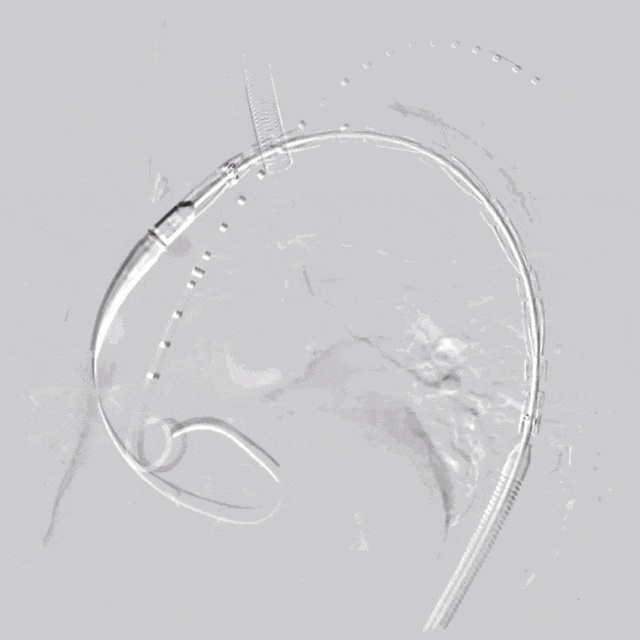

3. 沿左侧肱动脉Fustar内导入Fusmart可调弯导管及0.035"Terumo普通泥鳅导丝尾端,到达主动脉弓覆膜支架上方,调整角度,以尽量垂直角度透视下配合破膜,选入主体支架内,LSA导管内造影,多角度确认导丝头穿过主动脉支架覆膜。

泥鳅导丝怎么用符伟国/王利新教授团队:0.035"普通泥鳅导丝进行胸主动脉弓上分支原位开窗的病例分享_https://www.jmylbn.com_新闻资讯_第13张

LSA可调弯鞘内进可调弯导管

泥鳅导丝怎么用符伟国/王利新教授团队:0.035"普通泥鳅导丝进行胸主动脉弓上分支原位开窗的病例分享_https://www.jmylbn.com_新闻资讯_第14张

RAO方向确认导管

与大支架覆膜垂直

泥鳅导丝怎么用符伟国/王利新教授团队:0.035"普通泥鳅导丝进行胸主动脉弓上分支原位开窗的病例分享_https://www.jmylbn.com_新闻资讯_第15张

破膜成功

泥鳅导丝怎么用符伟国/王利新教授团队:0.035"普通泥鳅导丝进行胸主动脉弓上分支原位开窗的病例分享_https://www.jmylbn.com_新闻资讯_第16张

LSA导管内造影,确认破膜成功